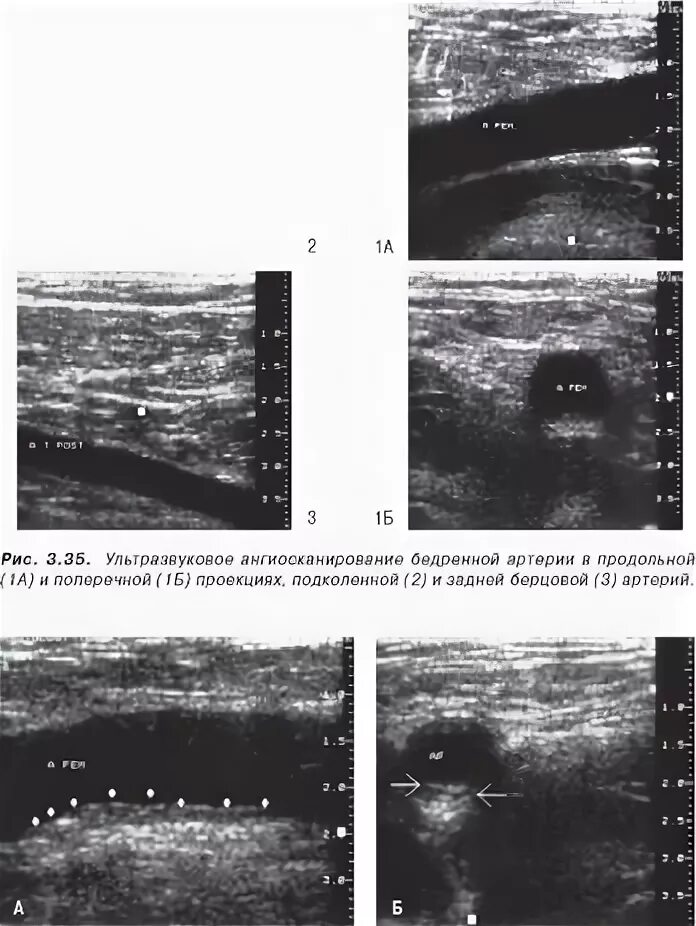

Атеросклеротическая бляшка узи